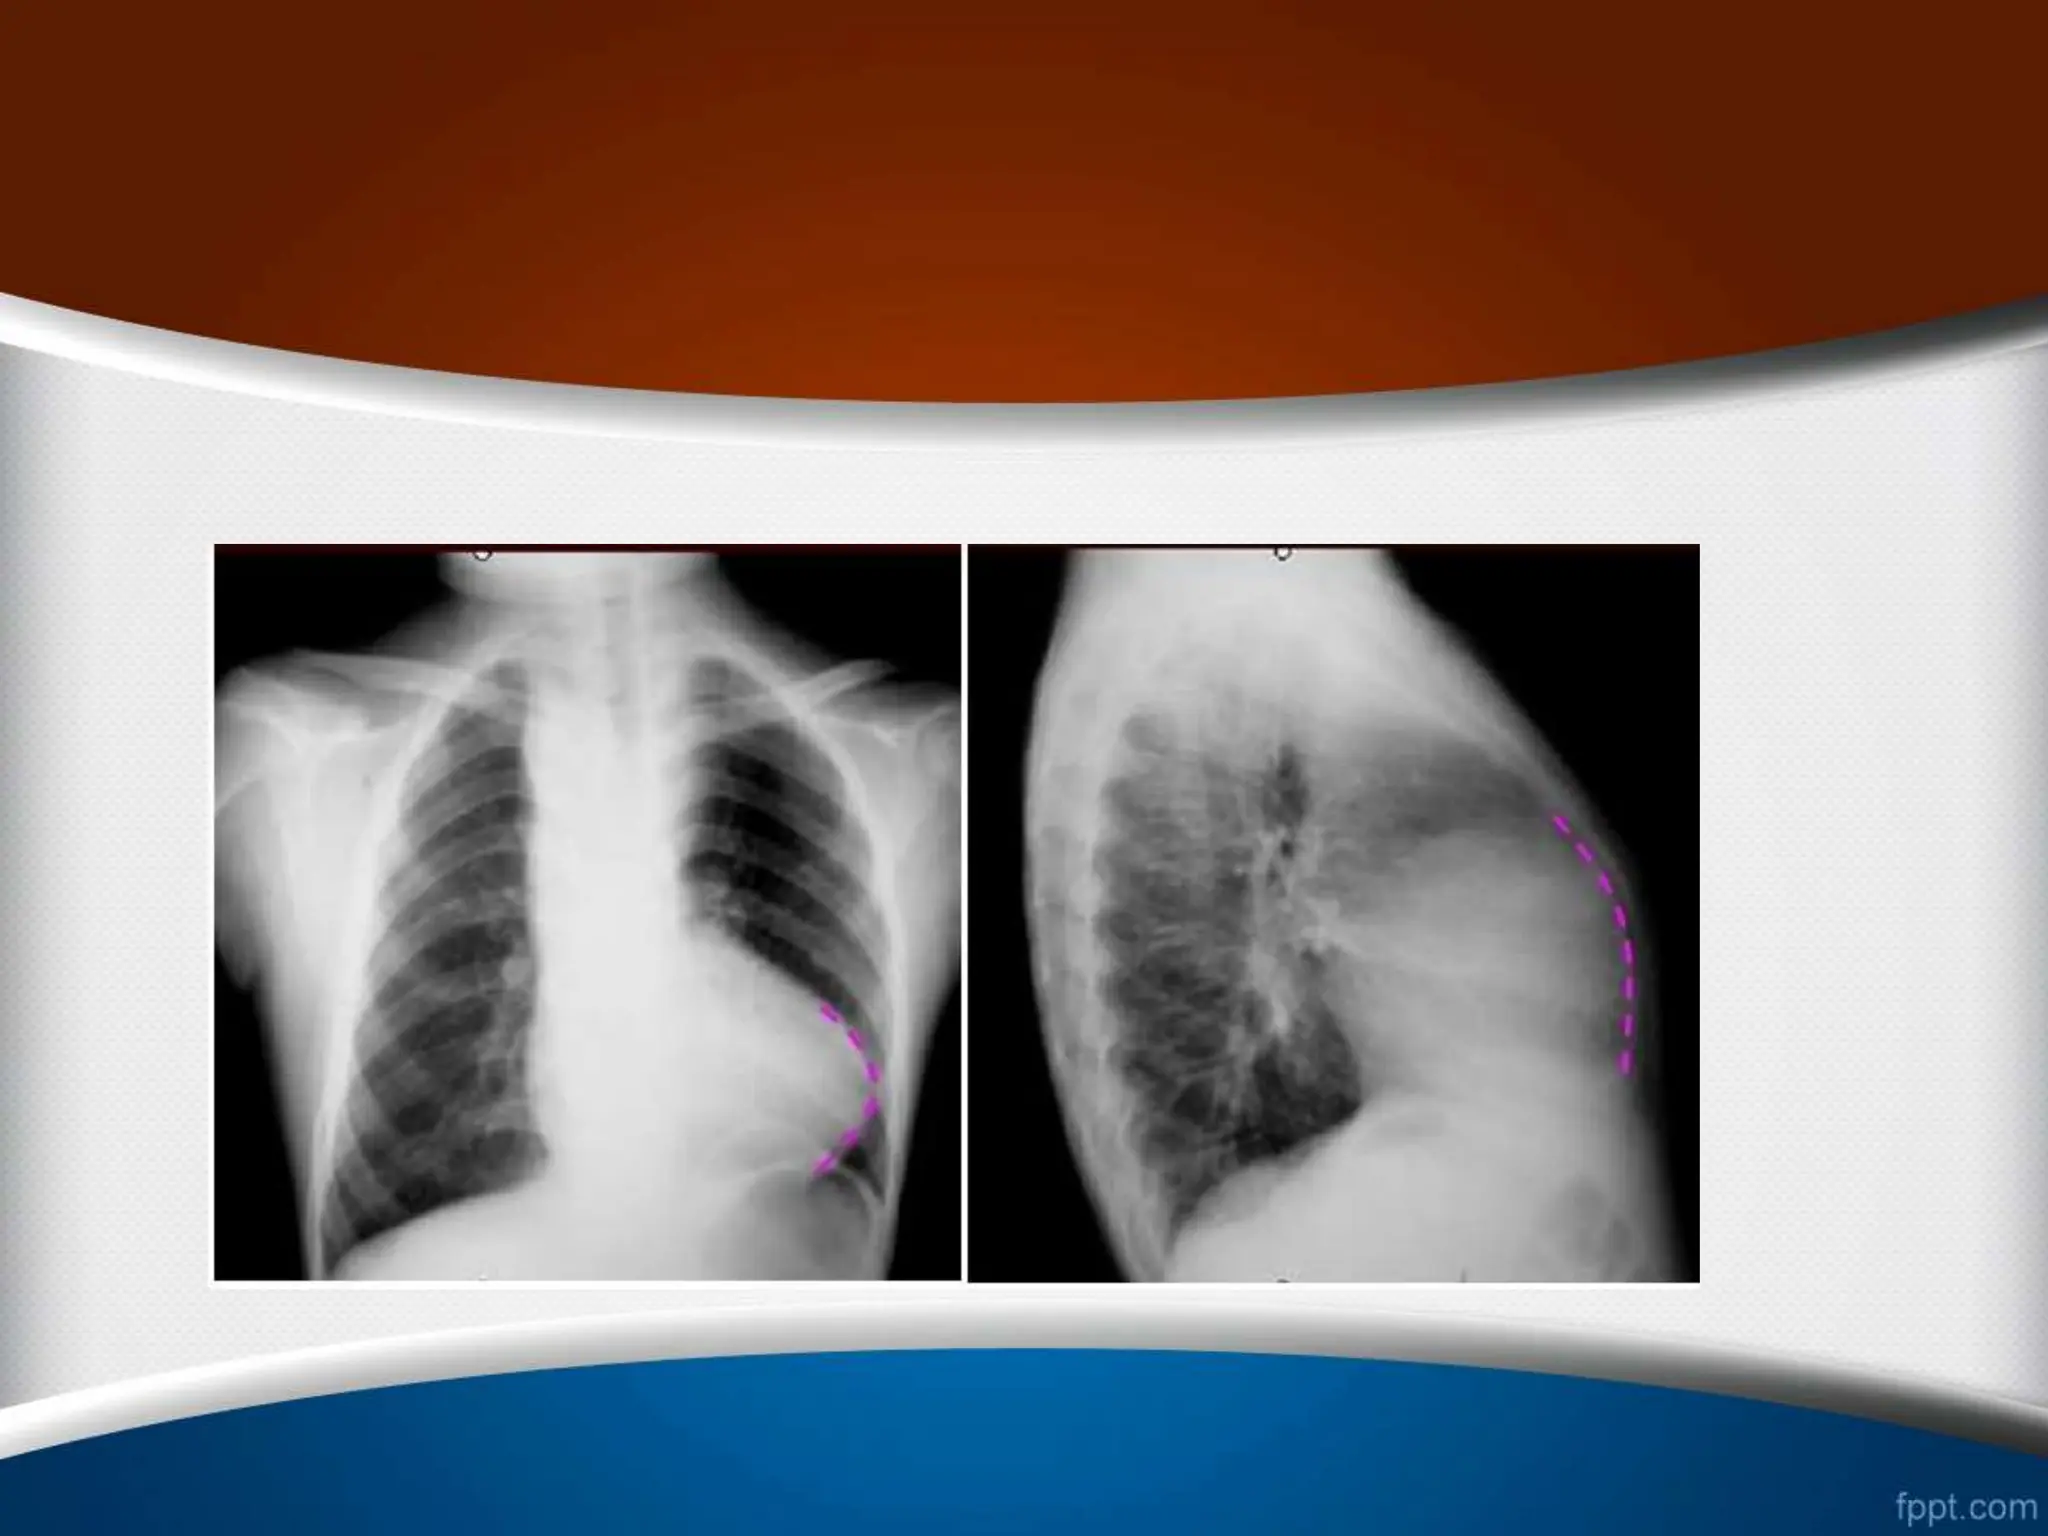

‫چپ‬ ‫دهلیز‬ ‫بزرگی‬